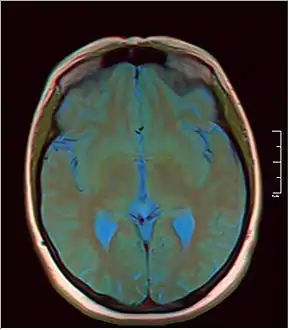

A pineal gland cyst is a usually benign (non-malignant) cyst in the pineal gland, a small endocrine gland in the brain. Historically, these fluid-filled bodies appeared on 1-4% of magnetic resonance imaging (MRI) brain scans, but were more frequently diagnosed at death, seen in 4-11% of autopsies.[1] A 2007 study by Pu et al. found a frequency of 23% in brain scans (with a mean diameter of 4.3 mm).[1]